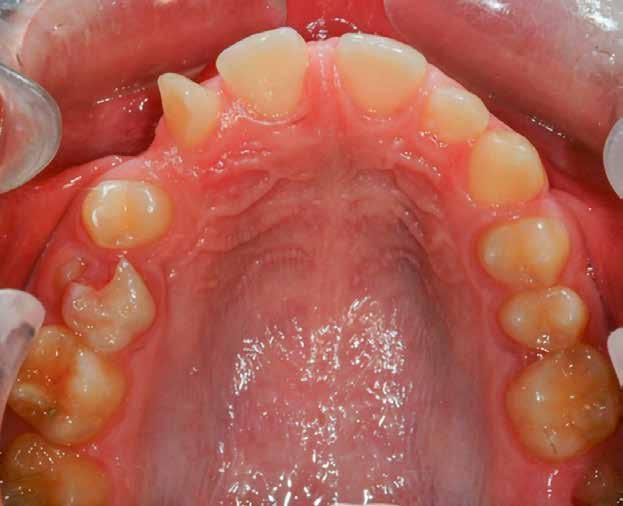

4. Felső okkluzális (tükör)

Az asszisztens most átvált a kisebb retraktorkészletre, és a páciens nyitott szájjal, V alakban behelyezi a retraktorokat, hogy a felső ajkakat oldalra és a fogaktól távolabb húzza. A klinikus a tükröt a szélesebbik végével befelé helyezi, hogy a fogív maximális szélességét rögzítse hátulról, és kissé lefelé húzza, hogy a teljes felső fogív látható legyen az utolsó jelenlévő zápfogig (10. ábra). a felvételnek a tükör síkjához képest 90°-ban kell készülnie a legjobb láthatóság és a vizuális torzítás elkerülése érdekében. A középső szájpadlásrésszel a szájpadlást a felvételen egyenesbe kell állítani. A retraktor minimális láthatósága a képen ajánlott, és a végleges fényképen lehetőleg ne látszódjanak ujjak.